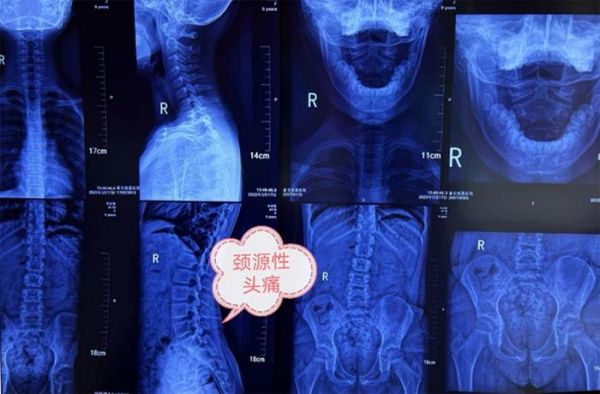

2、继发性头痛:顾名思义,就是一些其他的疾病导致的头痛,首先是头颈部的病变,如头颈部的外伤,颈椎病,肌肉劳损引起头痛。